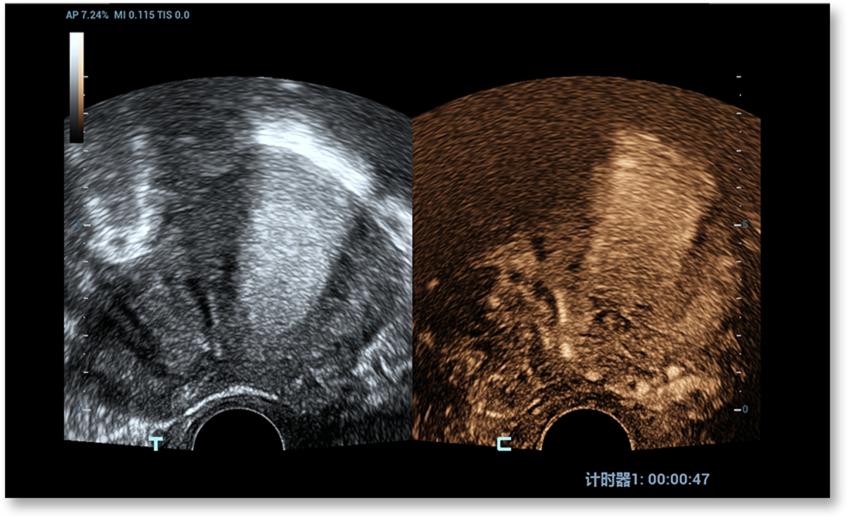

UWN+ (Ultra-Wideband Non-linear Plus) CEUS տեխնոլոգիան Nuewa R9-ին հնարավորություն է տալիս հայտնաբերել և օգտագործել թե՛ երկրորդ հարմոնիկան, թե՛ ոչ գծային հիմքային ազդանշանները՝ ստեղծելով զգալիորեն բարելավված պատկերներ, ինչը բարձրացնում է զգայունությունը և երկարացնում տեսագրության/դիտարկման տևողությունը՝ գինեկոլոգիական հիվանդությունները ավելի լավ հասկանալու համար։